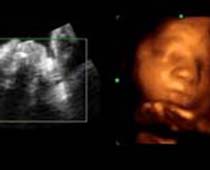

- Fetal Face Ultrasound Photos

- 3D Fetal Profile Ultrasound Scan Photos

- The Clinical Advantages of 3D and 4D Ultrasound

- Definition and Features of Four Dimensional Ultrasound

- Uses of 4D Ultrasound scan